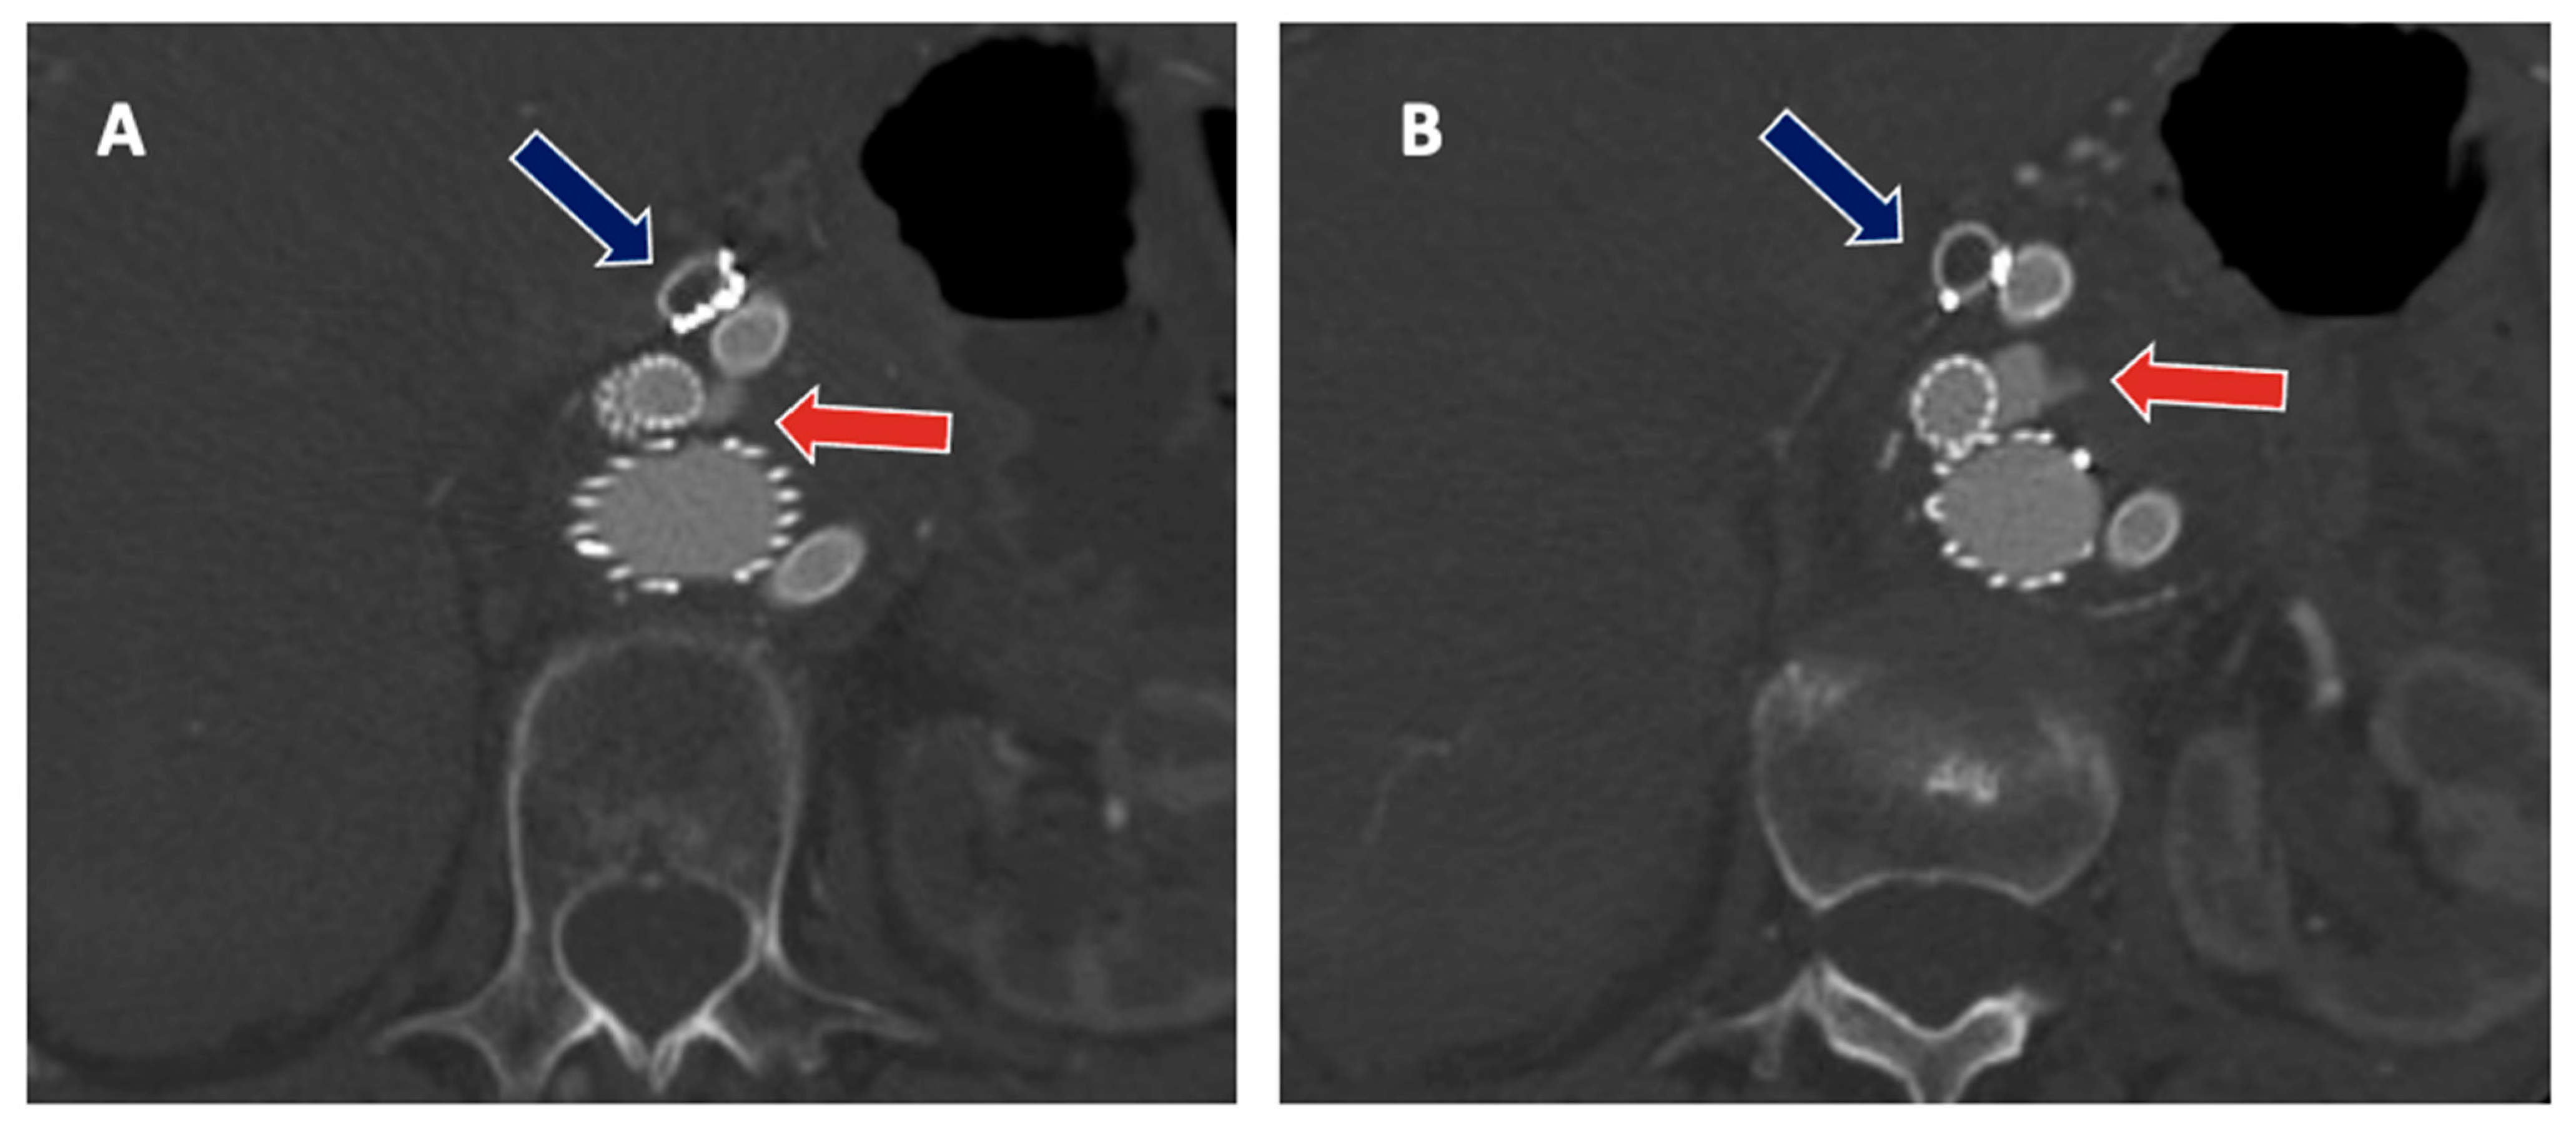

- Squizzato, F.; Antonello, M.; Forcella, E.; Coppadoro, C.C.E.F.S.; Colacchio, C.; Xodo, A.; Grego, F.; Piazza, M. Geometrical determinants of target vessel instability in fenestrated endovascular aortic repair. J. Vasc. Surg. 2022. [Google Scholar] [CrossRef]